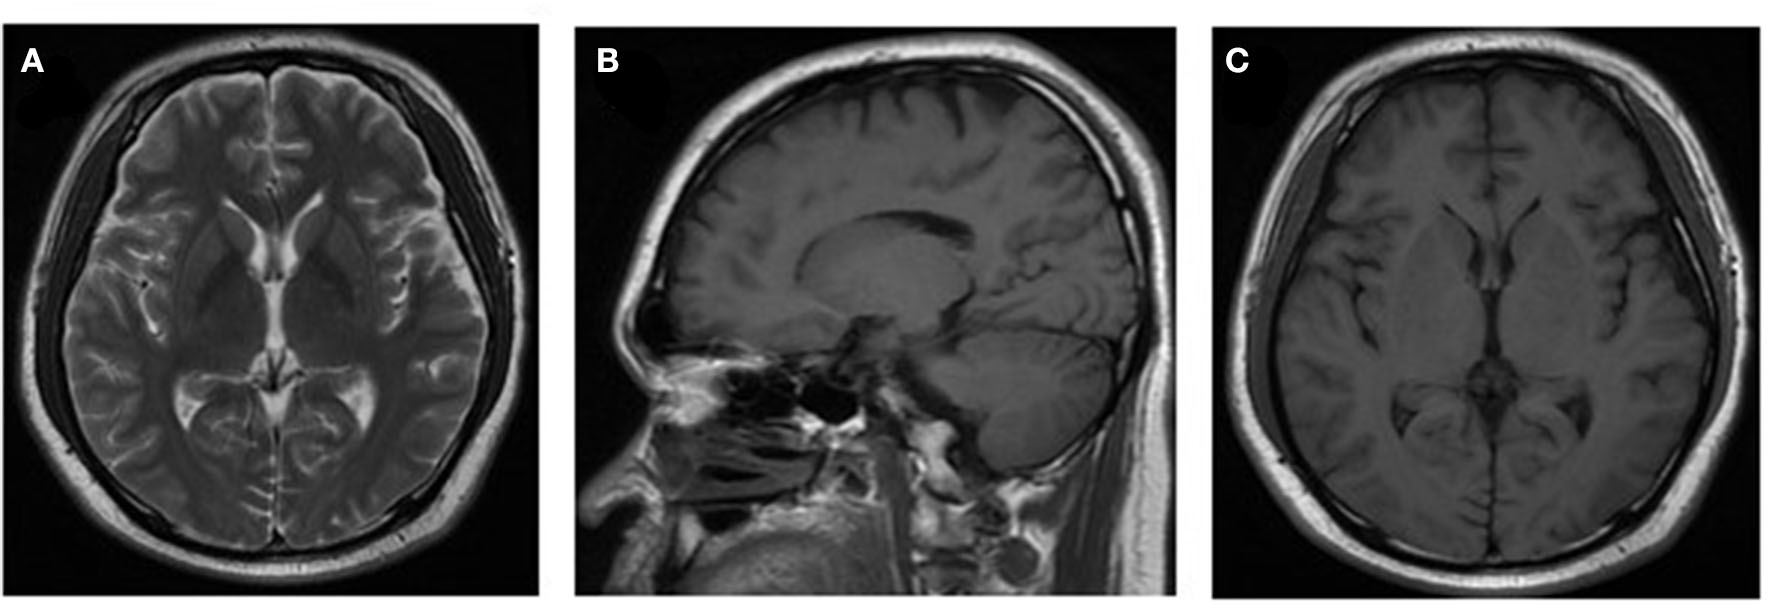

However, after 10 days of initial treatment, the review of CSF pressure revealed that the intracranial pressure was still > 300 mmH2O. On suspicion of unknown etiology, both peripheral blood and CSF samples of the patient were sent for mNGS, combined with CSF examined by traditional examinations too. The karyocyte count of CFS was 210 × 106/L (60% monocyte and 40% apocyte), erythrocyte count was 360 × 106/L, with a glucose level of 5.29 mmol/L. The protein level of cerebrospinal fluid was 4.39 g/L, the lactic level was 5.4 mmol/L, and the chloride level decreased to 105 mmol/L. Two sets of cultures of CSF, and also the test for EB virus antigen, Human cytomegalovirus antibody, Herpes simplex virus antibody, Cryptococcus antigen, and Toxoplasma antibody, were negative (Full laboratory testing in CSF is shown in Table 1). In addition, the results of echocardiography, vascular ultrasound, and MRI of the head were all unremarkable (Figure 1). However, within 24 h, mNGS detected 22 reads (A total of 19,870,653 sequence reads) corresponding to Brucella genus in CSF, but nothing was tested in peripheral blood. Subsequently, the identification of Brucella was confirmed by the SAT kit (Sinoreca, Beijing) in CSF and peripheral blood, antibody titers against Brucella in CSF and peripheral blood were 1:80 and 1:160, respectively. Therefore, the treatment was adjusted to doxycycline (0.1 g q8h), rifampin (0.45 g qd), and cefatriaxone (2.0 g ivgtt bid). After 20 consecutive days of the new treatment, his headache and blurred vision diminished, with body temperature returning to normal. The patient was discharged from the hospital with cefatriaxone (2.0 g ivgtt bid), doxycycline (0.1 g tid), and rifampicin (0.15 g tid) (The timeline of this case can be seen in Figure 2). About 2 months later, the patient returned to Shanghai for a lumbar puncture, and the pressure of cerebrospinal fluid was 210 mmH2O. The follow-up to maintain the oral anti-infective program, the total course of the treatment is about 6 months, symptoms of the patient have basically disappeared, the body temperature was stable, and antibiotics were stopped.

Figure 1

Neuroradiologic MRI. The MRI examination results of the patient were unremarkable (images shown in pictures A–C).

Although infection of Brucellar can be diagnosed by culture, serological test, and PCR-based tests, culture remains to be the gold standard for diagnosis (14). Actually, clinical microbiology laboratory culture for detecting Brucella of acute cases usually takes at least 5 to 7 days with a modern automated blood culture system, and protracted ones may need a longer time to obtain a definitive result (8, 14). The long incubation and low sensitivity hamper the detection of cultures and cause the delay in diagnosis, furthermore, the safety of the laboratory is still a worldwide concern. Of course, the serological test is another widely used pathogen diagnostic method of human brucellosis that has drawbacks too, such as insufficient specificity and poor repeatability. In recent years, nucleic acid amplification tests have been developed into a new tool with excellent sensitivity and specificity, and regarded as supplemental support to culture, nevertheless, it is limited to the known gene sequence of pathogenic microorganisms and remains have high false positivity in the recovered patients. Therefore, the selection of an appropriate pathogen diagnostic method is essential for the diagnosis of brucellosis, especially in patients with CNS involvement. In this case, consciousness of the patient was lost and was in poor health status upon admission, and the MRI examination results of the patient were unremarkable, which made it more difficult for us to judge the central infection. We decided to send the CSF sample for mNGS directly without waiting for the culture of it. After a trade-off analysis between the benefits of treatment and the risk of false discovery of B. melitensis, initial treatment was made immediately based on the result of mNGS before confirmatory tests were completed. The patient was treated with doxycycline, compound sulfamethoxazole tablets, and amoxicillin-clavulanic acid for anti-infection as an initial treatment. The treatment effect was valuated from the number of unique reads in the CSF sample of October 16, 2020 and October 26, 2020, after 10 days of treatment the number of B. melitensis unique reads decreased to 0 and the number of Brucella unique reads decreased from 199 to 22. More and more cases suggested that mNGS could be implemented for monitoring the progress of the disease and evaluating therapy effects. Furthermore, the multiple symptoms of the patient were relieved. Due to Brucella was not the main cause of CNS infection, and the atypical clinical presentations of the patient, tended to be misdiagnosed or inappropriately treated. This case showed that using mNGS for inspecting the possible etiology of CNS infection was the right choice.